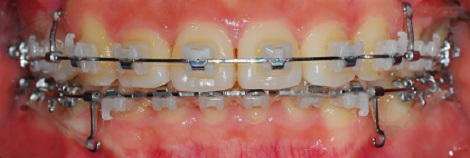

<정면 치아 사진>

가끔 치과 쌤이 고무줄로 예술을 하는듯ㅋㅋㅋ

신기했습니다.